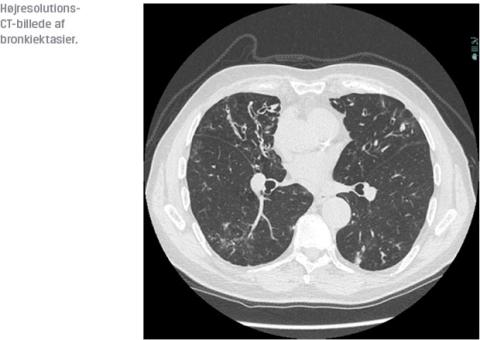

Diagnosen stilles ved HRCT (typisk med en koronal snittykkelse på 1 mm), som viser dilaterede vægfortykkede bronkier, der er større end den ledsagende arterie.